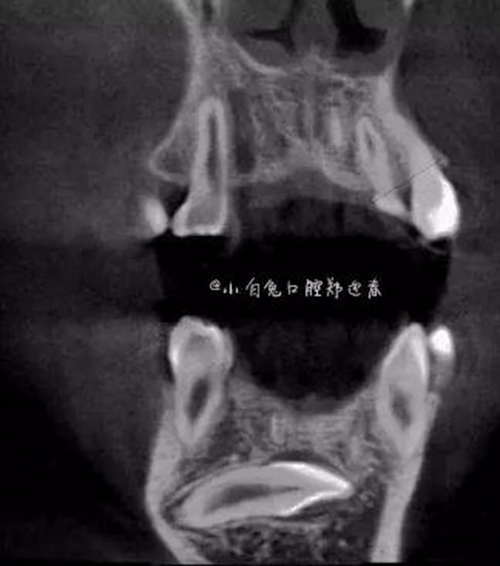

本案:患兒,女,14歲,因牙齒矯正來院,檢查見83滯留,43未見萌出,拍片發(fā)現(xiàn):43埋伏阻生于31、41、42根尖下方,按照正畸診療計(jì)劃,擬行43拔除術(shù)。

CBCT顯示